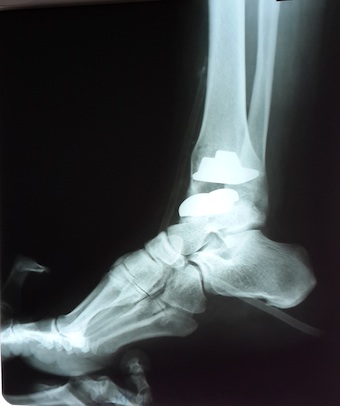

კიდევ ერთი წარმატებული ოპერაცია, გერმანული კომპანია implantcast-ის კოჭ-წვივის იმპლანტით ჩანაცვლდა დაზიანებული…